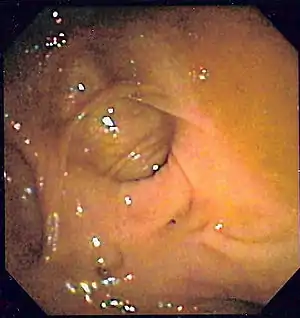

![]() | |

| Diverticulosis as seen endoscopically | |

Diverticulosis is defined by the presence of multiple pouches (diverticula) in the colon.[22] In people without symptoms, these are usually found incidentally during other investigations.

- Colonoscopy will show the diverticulum and rule out malignancy. A colonoscopy should be performed 4–6 weeks after an acute episode.